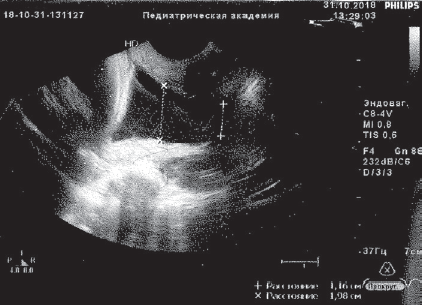

В анализах: общий белок крови 59 г/л, СОЭ 34 мм/ч, лейкоцитарный индекс интоксикации (ЛИИ) 2,6 усл. ед. (норма до 1,5), лейкоцитурия до 10 в поле зрения. Остальные анализы в норме. По данным УЗИ предполагаемая масса тела (МТ) плода 1403 г, плацента по передней стенке матки, 1-й степени зрелости, амниотический индекс 123 мм, шейка матки укорочена до 11 мм, цервикальный канал воронкообразно расширен на всем протяжении до 11–19 мм, выполнен до наружного зева плодным пузырем. Данные кардиотокографии и допплер-исследования кровотока в маточно-плацентарном пространстве в норме.

Получала сохраняющую беременность терапию с подключением трех сеансов мембранного плазмафереза (МПА) с возвратом гепаринкриомодифицированной аутоплазмы (при двух МПА по 200 мл), 12 сеансов ФК ультрафиолетовыми (№ 6) и лазерными (№ 6) лучами, без осложнений. После курса лечения анализы крови нормализовались, по данным УЗИ картина улучшилась, появилась сохранная часть шейки матки 6 мм, вероятно, за счет снижения внутриматочного давления в каудальном направлении. Пролабирования плодного пузыря за пределы наружного зева не визуализировалось в зеркалах и при УЗИ (рис. 1, 2).

Рис. 1. Данные ультразвукового исследования пациентки Ч., 30 недель беременности, до курса эфферентной терапии

Fig. 1. Ultrasonic examination of patient Ch., 30 weeks of gestation, before efferent therapy